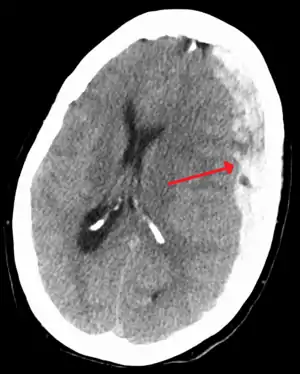

![]() Субдуральна гематома позначена стрілкою Субдуральна гематома позначена стрілкою | |

- Наявність видимої субдуральної гематоми на КТ та МРТ